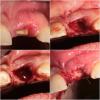

fmn Опубликовано 6 октября, 2013 Поделиться Опубликовано 6 октября, 2013 Здравствуйте, уважаемые коллеги. это мой первый пост на этом ресурсе. так что прошу не пинать сильно не судить строго. Вчера делал небольшую хирургию, надеюсь, интересную для посетителей форума. Пациентка - чудесная женщина средних лет пожаловалась на перелом корня центрального резца, который до этого был восстановлен композитной реставрацией на внутриканальном штифте. На КТ - небольшая фенестрация вестибулярной стенки и потеря костной ткани в области дистальной контактной поверхности, что склонило чашу весов в процессе принятия решения в сторону отсроченной имплантации. По поводу выбора техники я долго колебался - первоначально предложил удаление и аугментацию ССТ тоннельным методом с вестибулярной стороны. затем передумал и, в итоге решил отложить это до этапа имплантации (т.к. дистальный сосочек может уйти и на этапе имплантации будет возможность его аугментировать), а в качестве подготовки провести аугментацию костным материалом и толстым СДТ. Ссылка на комментарий

fmn Опубликовано 7 октября, 2013 Автор Поделиться Опубликовано 7 октября, 2013 В лунке Gen Oss Ссылка на комментарий

fmn Опубликовано 7 октября, 2013 Автор Поделиться Опубликовано 7 октября, 2013 можно было сразу болтСогласен, раньше я сам бы сразу поставил. Сейчас последовал рекомендации Цура при наличии дефектов вестибулярки и интерпроксимальной делать отсроченно. Ссылка на комментарий